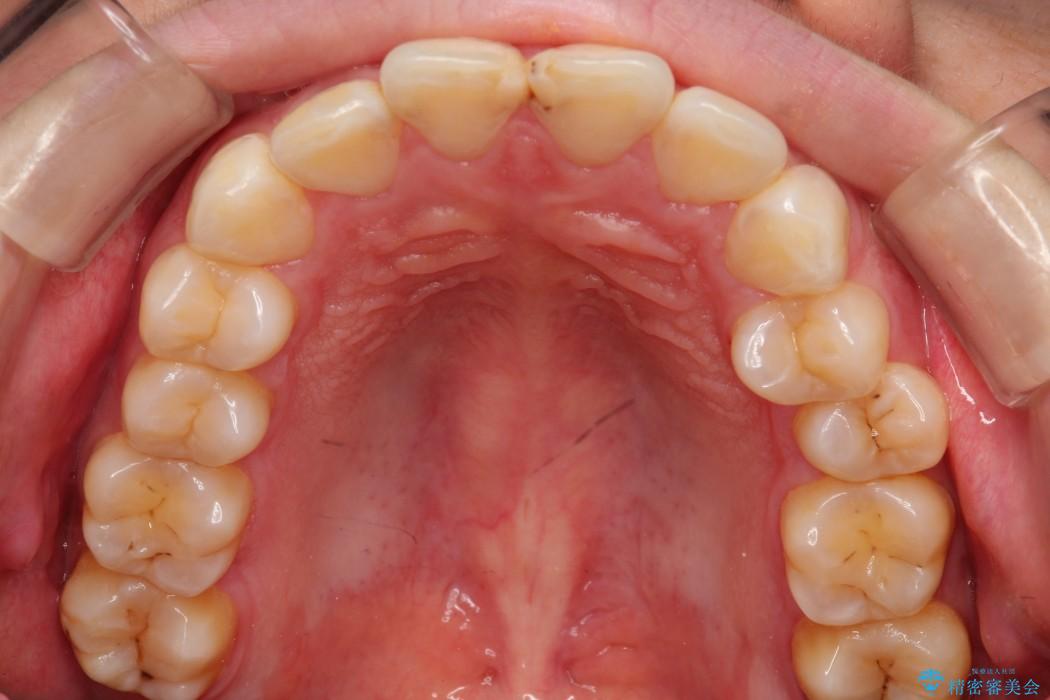

【20代女性】出っ歯の矯正 治療例

口元が出ていることを気にされて来院されました。

治療費の安い矯正治療を希望されていたため、メタルのワイヤー装置にて治療する計画にしました。また、歯みがきが苦手だったため、矯正治療をする前に徹底的にブラッシング指導を行いました。

出ている歯を引っ込めるためのスペースを作るため、上下左右の小臼歯を抜歯し、ワイヤー矯正を行いました。治療後は、口元がスッキリとしたことで患者様にも喜んでいいただきました。